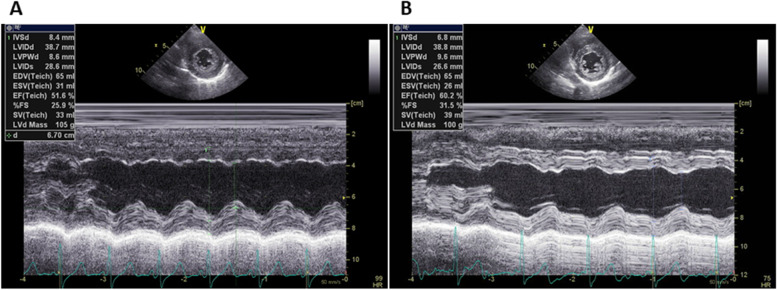

Five days after onset, brain MRI showed regions of hyperintensity in the right frontal lobe, bilateral parietal cortex and subcortex, and bilateral cerebellar lobes on FLAIR images (Fig. 1A). In addition, although the apparent diffusion coefficient (ADC) map showed elevations (Fig. 1B), no region of hyperintensity was observed on the diffusion-weighted image (DWI), suggesting angioedema (Fig. 1C). No abnormal findings were observed on brain magnetic resonance angiography (MRA) at the time of onset of the first headache (Fig. 2A). However, four days after the onset, multiple cerebrovascular spasms were observed, in which alternate contractions and dilations of several main arteries occurred (Fig. 2B). On the electrocardiogram (ECG) five days after the onset of the first headache, ST depression was observed in limb leads II, III, and aVF, and in the chest leads V3 to V6 (Fig. 3A). Ultrasound cardiography (UCG) showed a hypokinesis at the base of the side of intraventricular septum, with a slight decrease in ejection fraction (EF = 51.6%) and in fractional shortening (FS = 25.9%) (Fig. 4A). Although no symptoms of angina were observed 5 days after onset of first headache, left ventricular hypofunction leading to impending heart failure was suspected. Therefore, a calcium channel blocker and a nitrate were administered.

Based on her clinical course and imaging findings, she was diagnosed with reversible cerebral vasoconstriction syndrome (RCVS) with cardiac involvement. We administered 5 mg of the calcium channel blocker amlodipine besylate, 25 mg of nitroglycerin, and 500 mg of the antiepileptic drug levetiracetam. The hyperintense regions on FLAIR images completely disappeared 23 days after onset of first headache. She showed no exacerbation of heart failure, and the ECG (Fig. 3B) and UCG (Fig. 4B) findings were found to be normal eight days after onset of first headache. To avoid the risk of vascular spasm by iodinated contrast medium, we did not perform cardiac catheterization or coronary computed tomography (CT)-angiography until her RCVS was fully controlled. Since no recurrence of symptoms was observed after the treatment, we performed coronary CT-angiography seven months after the onset, which showed no significant vasoconstriction in any coronary artery (Fig. 5A, B).

A notable feature of this case was that reversible cardiac involvement occurred concomitantly with RCVS. Despite the absence of chest symptoms, an increase in serum BNP levels, ST-T changes on ECG, and decreased EF and FS on UCG were seen and improved three days after therapy was started. This implies that there is cardiac involvement caused by Takotsubo cardiomyopathy or abnormalities in coronary arteries. So far, it has been reported that in a retrospective study 68 cases, from which 18 had patients had undergone UCGs around the period of active RCVS. Among them, three female patients who had no coronary artery disease or heart failure presented with wall motion abnormalities on UCG [ref. 9]. This report concluded that cardiac ventricular abnormalities may be a part of the RCVS spectrum. In another report, a middle-aged female patient with RCVS showed coronary artery spasm. The patient, with repetitive chest pain and transient wall-motion abnormalities on UCG, had experienced a thunderclap headache, and diffuse cerebral vasoconstriction was revealed on cerebral angiograms [ref. 10]; in this case, RCVS had developed after repeated coronary artery spasm. However, our case presented both cerebral and cardiac lesions almost coexisted. We did not perform the coronary angiography to avoid the adverse effect such as vasoconstriction by the contrast medium; however, coronary vasospasm may have occurred by the mechanism like that of cerebral vasospasm. Whilst, based on the UCG findings and ECG changes that cannot be explained by the distribution of coronary arteries, catecholamine cardiomyopathy such as reverse Takotsubo cardiomyopathy may have occurred by severe pain from thunderclap headache [ref. 11].